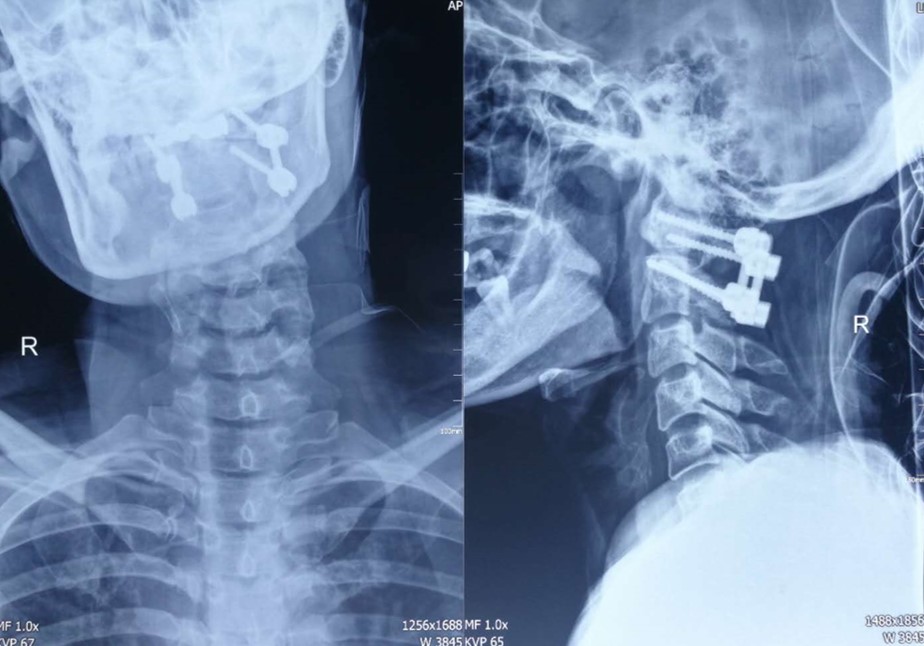

兰大二院骨科二病区联合神经外科完成一例高难度寰枢椎椎弓根螺钉内固定、椎板切除减压、椎管内肿瘤切除术

近日,我院骨科二病区主任张海鸿团队联合神经外科潘亚文教授,为一位患有上颈椎椎管内肿瘤的51岁女性患者实施了高难度、高风险的寰枢椎椎弓根螺钉内固定、椎板切除减压、椎管内肿瘤切除术。

患者入院后,经颈椎三维CT、颈椎平扫及增强核磁、椎动脉造影等检查,明确无椎动脉变异,具备了手术的基本条件。因为患者肿瘤位置较高,靠近延髓呼吸中枢,瘤体较大,严重压迫脊髓,手术切除可能引起脊髓缺血再灌注损伤导致高位脊髓损伤而影响生命安全,因此该手术属于脊柱外科高风险高难度手术。

手术顺利实施后,患者转往神经外科ICU进行稳定治疗,术后第三天患者转回骨科2病区接受康复治疗,术后一周左右患者即可佩戴颈托下地活动,各项指标恢复正常后,患者办理出院。